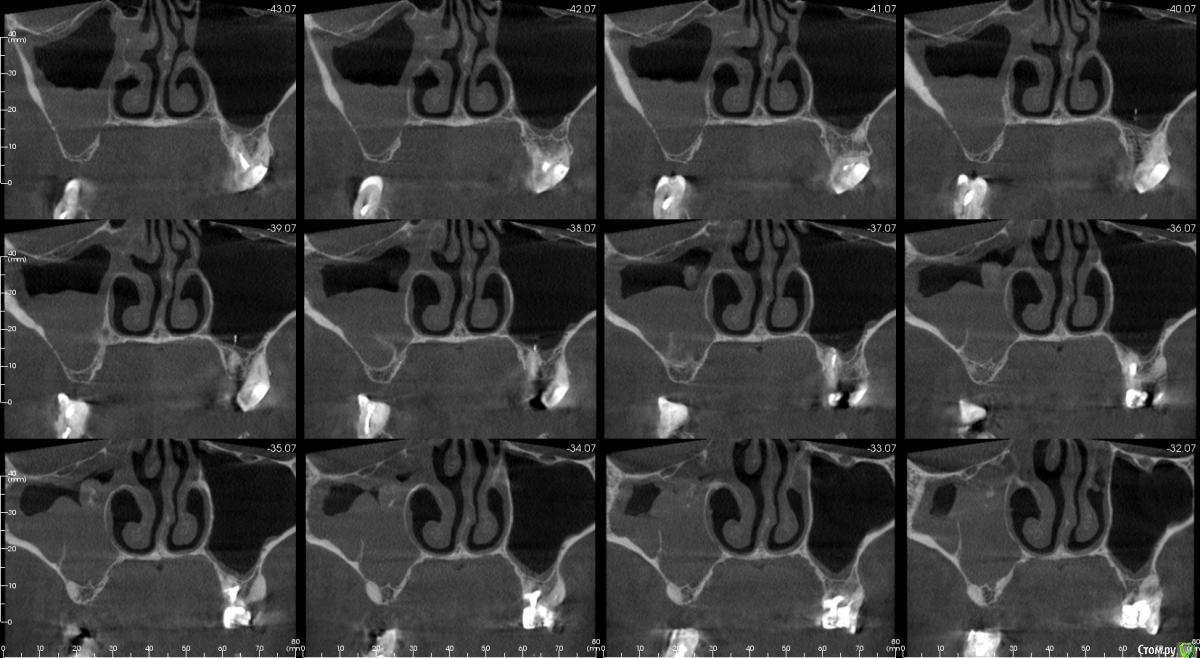

Irouil Опубликовано 16 апреля, 2018 Поделиться Опубликовано 16 апреля, 2018 Имхо - нет. ЛОР КТ смотрел вообще? Тут может быть что угодно, от уровня жидкости до инвертированной папиломы. Ссылка на комментарий

kamranchick Опубликовано 16 апреля, 2018 Автор Поделиться Опубликовано 16 апреля, 2018 Смотрел, и такое заключение дал. вот меня и смутило, в верхней трети около соустя вообще вкрапления какие то есть )) Ссылка на комментарий

егорджан Опубликовано 16 апреля, 2018 Поделиться Опубликовано 16 апреля, 2018 ретенционная киста, а за ней гайморит)) Ссылка на комментарий

Irouil Опубликовано 16 апреля, 2018 Поделиться Опубликовано 16 апреля, 2018 Смотрел, и такое заключение дал. вот меня и смутило, в верхней трети около соустя вообще вкрапления какие то есть ))Больше всего похоже на грибковое тело, и вкрапления эти намекают, и контуры затенения. Пунктировать не стал ЛОР это? 1 Ссылка на комментарий

kamranchick Опубликовано 16 апреля, 2018 Автор Поделиться Опубликовано 16 апреля, 2018 Больше всего похоже на грибковое тело, и вкрапления эти намекают, и контуры затенения. Пунктировать не стал ЛОР этоОтправил для санации, он написал вот это только( что ретенционная, но потом я внимательно начал крутить туда сюда и вот засомневался Ссылка на комментарий

Irouil Опубликовано 16 апреля, 2018 Поделиться Опубликовано 16 апреля, 2018 По большому счету; какая разница то? Вы же пациентку ради синус лифта (насколько я понимаю) отправляли, в таких условиях его не сделать. Там даже если соустье толщиною с пенис Трампа будет, все равно его ткани+отек перекроют после синуса. Так или иначе пазуху надо оперировать, только если ЛОР не считает что ретенционная киста - одонтогенная и пройдет при санации первичного очага) Ссылка на комментарий